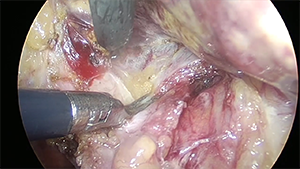

腹腔镜解剖性肝S8段切除

作者:陈实 | 作者单位:福建省立医院

发布时间:2020-09-03 21:54:31